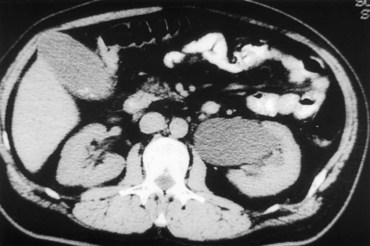

CT scan is frequently obtained for any patient presenting with acute flank pain (Fielding et al, 1997; Dalrymple et al, 1998; Vieweg et al, 1998) (Fig. 41–3). Moreover, CT scans provide detailed anatomic and functional information to aid in diagnosis of UPJ obstruction (Fig. 41–4A-C). Both ultrasonography and CT scanning also have a role in differentiating acquired causes of obstruction such as radiolucent calculi or urothelial tumors. In neonates and infants, the diagnosis of UPJ obstruction has generally been suggested either by routine performance of maternal ultrasonography or by the finding of a flank mass. In either setting, renal ultrasonography is usually the first radiographic study performed. Ideally, ultrasonography should be able to visualize dilatation of the collecting system to help differentiate UPJ obstruction from multicystic kidney and determine the level of obstruction. UPJ obstruction and multicystic kidneys are distinguishable in the majority of cases by ultrasound alone. With UPJ obstruction, the pelvis is visualized as a large, medial sonolucent area surrounded by smaller, rounded sonolucent structures representing dilated calyces. At times, dilated calyces will be seen connecting to the pelvis via dilated infundibula (Fig. 41–5).

Figure 41–3 Noncontrast CT scan performed as the initial radiographic study in a patient presenting with left flank pain revealed hydronephrosis to the level of the ureteropelvic junction (UPJ). No calculus was visualized, and a presumed diagnosis of UPJ obstruction was considered. This proved correct on subsequent radiographic studies.

Figure 41–4 A, Contrast-enhanced CT scan identifies a classic ureteropelvic junction (UPJ) appearance in early-phase imaging. B, Early images reveal normal nephrogram and delayed filling of the obstructed, dilated UPJ. C, Delayed images demonstrate holdup of contrast drainage on the right compared with the normal left side.